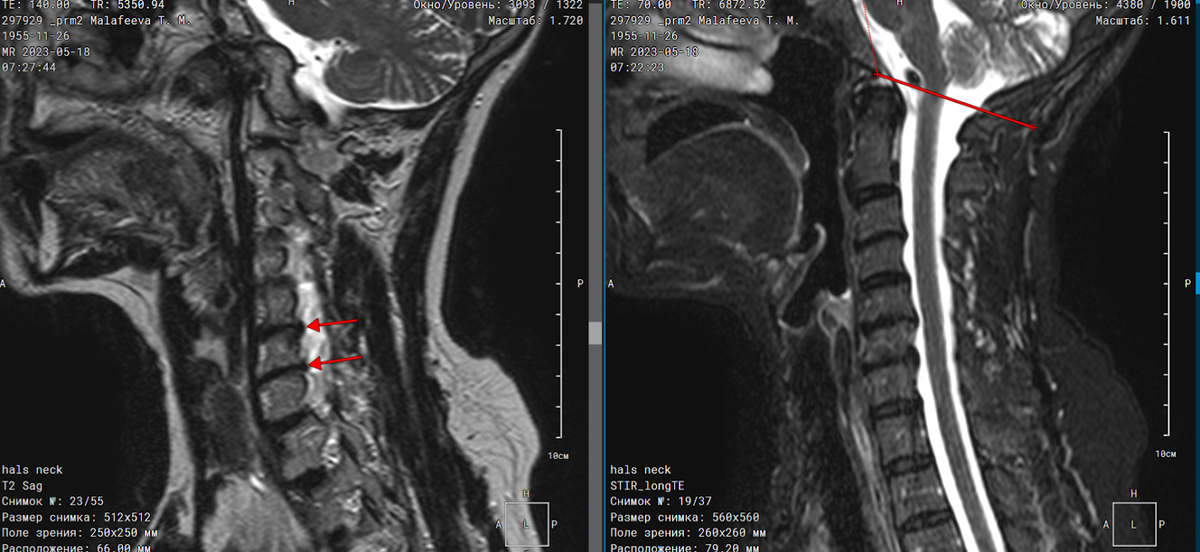

Положение шейного отдела позвоночника правильное. Шейный лордоз выпрямлен. Признаков костнодеструктивных изменений не выявлено. Миндалины мозжечка расположены в пределах большого затылочного отверстия. Определяются дорзальные экструзии межпозвоночных дисков С5-С6, С6-С7, размером до 0,27 см. Спинной мозг на уровне визуализации не изменен.

Рис. 1. Сагиттальная Т2 и Stir программы: стрелками указаны экструзии дисков; линия ограничивает пределы большого затылочного отверстия.